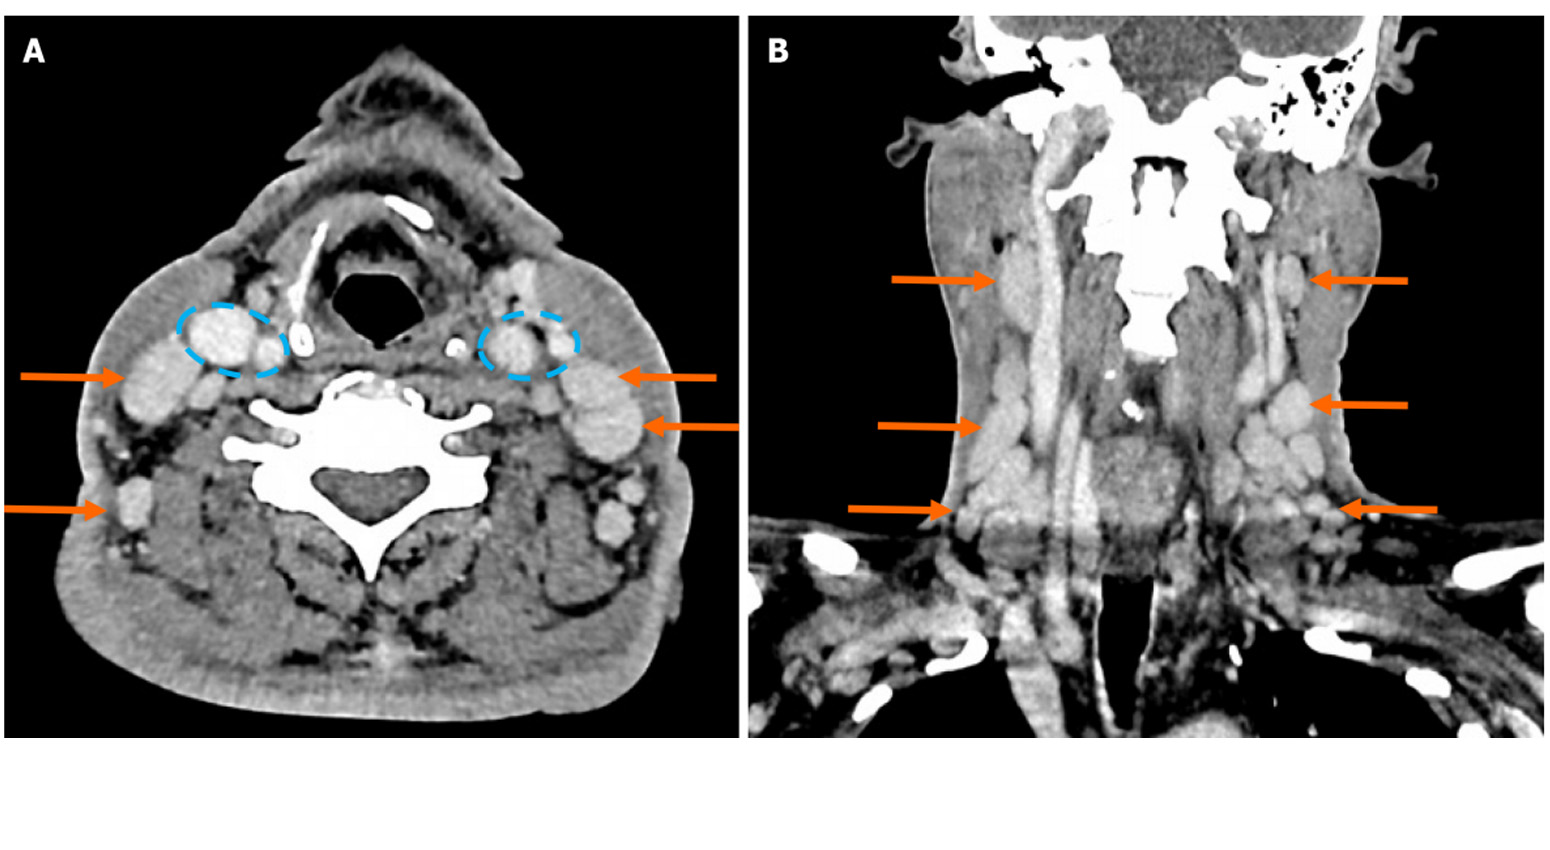

- Contralateral metastatic papillary thyroid carcinoma and com... 2025-10-11